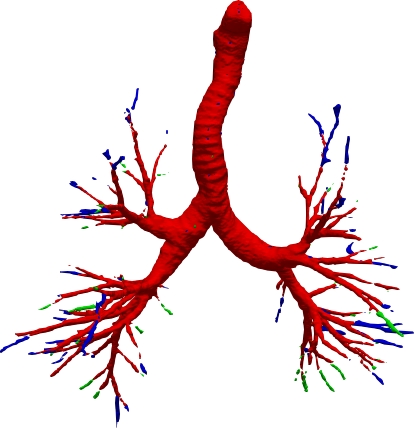

However, current state-of-the-art methods of lung organ segmentation still face several challenges and aspects for improvement. Firstly, the unlimited voxel values, multi-site imaging discrepancy and class imbalance in lung organ images can lead to false-negative and leakage issues in prior segmentation methods, which badly influences the critical early diagnosis of imperceptible lung diseases, e.g., lung fibrosis, nodule and hypertension, etc. Secondly, the presence of numerous slender branches, e.g., bronchioles and arterioles, which are easily lost during the recycled down/up-sampling procedure in Fig. 1, can result in discontinuity, detail loss, and coarse mask predictions. Thirdly, most CNN-based medical segmentation methods treat all points equally during the mask rendering stage, overlooking the vulnerability of border points in Fig. 1 (f) and the importance of explicit border modeling. Lastly, while Vision Transformer (ViT) has shown promise in computer vision tasks [1, 4], its quadratic operation complexity limits its application in 3D high-resolution CT images due to hardware constraints. Meanwhile, most specific datasets for medical image analysis are small and scarce due to laborious manual annotation and privacy protection, which badly restricts the potential of transformer-based top-tier methods.

2.2 Global-Local Cube-tree Fusion

To the best of our knowledge, most mask render-based two-stage semantic segmentation methods [6, 21] operate equally on all dense points of the coarse masks to improve the final performance, which is unnecessary to focus much on the already correctly predicted points. As shown in Fig. 1 and according to our statistical error analysis, most very vulnerable points occur on the object border due to the information loss caused by down-sample operation in the encoding process, especially for the innumerable bronchioles or arterioles in the tree-like structures. Thus, we only focus on the border vulnerable points and propose the novel global-local cube-tree fusion module. Specifically, (1) we “recycle” the down-sample and up-sample operations to produce masks and , and evaluate the absolute difference of them in Fig. 1 to get the border vulnerable points for the -th layer; (2) as shown in the top-right side of Fig. 2, we build the cube-tree of the -th point by extracting the local contextual features of {26, 27}-neighbors of the {, +1}-th layers respectively, which are defined as the cube without and with centroid. For the last layer, it is of note that we extract the 27-neighbors’ local contextual features in the adjacent layer -1; (3) we flatten features in the spatial dimension and project them as well as centroid feature into three vectors , which are separately related to the fine grain, coarse grain local context information and cube-tree centroid feature; (4) global airway or artery features from the distribution of the whole dataset is also very important, hence, we introduce the learnable global features to yield the projected global features , where is the embedding dimension; (5) we fuse the four features into as follows:

where [0, 1] are the learnable coefficients to balance the importance of each feature; (6) we lastly add the feature to the relative position embedding features (retaining the topology information for inductive bias) for the voxel-wise decoding and refined prediction. Obviously, our proposed global-local cube-tree fusion module focuses merely on all border vulnerable points in Fig. 1(f) rather than all regular dense points in Fig. 1(c), which is more related to the lung organ regions. Experimental results demonstrate the efficacy of this design.

We qualitatively analyze our method on four challenging lung organ datasets. In Fig. 5, SFCN [19] suffers from severe false positives and some false negatives, especially for the big green areas of airway leakages. WNet [22] is mainly influenced by false negatives on the main trachea. For the Fibrosis dataset at the third row, it also encounters the false negative problem in the terminal bronchioles moderately. FANN [10] bears the slight discontinuity issue of false negative in the terminal bronchioles of BAS dataset, and the severe discontinuity and airway leakage problems on the more challenging Fibrosis benchmark. Instead, due to the above two novel modules, our method can solve the defects of false negative, discontinuity, and leakages faced by past advanced methods. Besides, the results on PARSE22 artery dataset in supplementary Fig. 6 also proves this.

Comparison on PARSE22 dataset. This dataset is more challenging due to more dense small bronchioles shown in supplementary Fig. 6. However, our method still reaches the best weighted average multi-level dice of 84.96% in Table 2 compared against some advanced methods via the official evaluation. As you can see, the remarkable gain comes from the “branch artery”, which maintains the consistency with above airway segmentation.